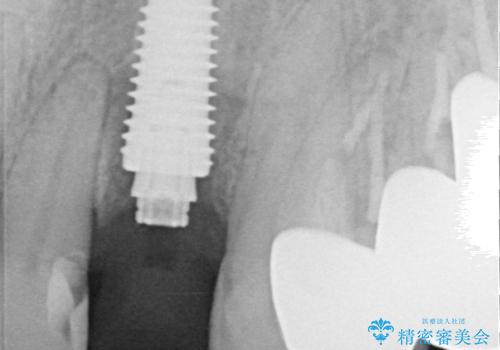

抜歯、インプラント埋入、仮歯の装着が同時に可能な1DAYインプラントが適用可能と判断されたため、インプラントによる補綴治療を行うこととしました。

前歯のインプラント治療は、従来の抜歯から数ヶ月待機する手法では、骨造成や歯肉移植など付随の処置が多く必要となり、費用、期間、身体的負担のいずれもが多大となります。

抜歯時にインプラントを埋入することでそれらの負担を大きく軽減させることが可能です。